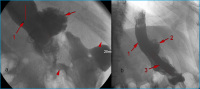

AGB

Abbildung 8: Bandleck nach AGB: Kontrastmittelinjektion in das Injektionsreservoir (1) mit wasserlöslichem, nichtionischem, isoosmolarem Kontrastmittel, über eine liegende Huber-Nadel (2). Der Katheter ist am Übergang zum Injektionsreservoir abgeknickt (3), wodurch es zu einem Kontrastmittelleck (4) kommt. Das Kontrastmittel der letzten Bandfüllung im Magenband (5) ließ sich am Beginn der Untersuchung nicht absaugen.

Keywords: GastroenterologieMagenbandRadiologie